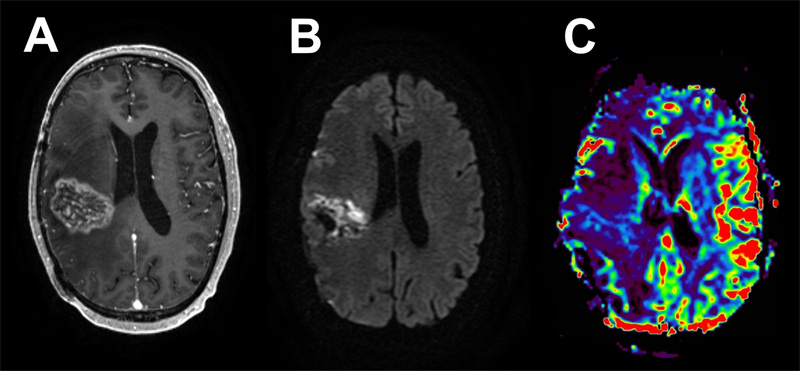

Five weeks later, the patient underwent a right temporo-parieto-occipital craniotomy for tumor resection. His postoperative course was complicated by a seizure upon awakening with right frontal venous infarct and layering remote cerebellar hemorrhage. He experienced weakness in his left upper and lower extremities and was discharged to a rehabilitation facility with antiepileptic and steroid medications. At 5 months follow-up, the patient had recovered his motor function with no additional seizures, was able to walk over a mile per day without assistance and was tolerating adjuvant chemoradiation. Subsequently, post-treatment MRIs demonstrated a heterogeneously enhancing, centrally necrotic mass in the right temporo-parietal tumor bed with no associated hyperperfusion, characteristic of evolving pseudoprogression. These findings were associated with marked hemispheric cerebral edema refractory to steroid treatment and requiring bevacizumab (Fig. 2).

Figure 2: Case 1 Post-treatment imaging findings. An 8-month post-operative MRI following chemo-radiation showed evidence of pseudoprogression with significant associated cerebral edema. Axial T1 post-contrast (A) shows a heterogeneously enhancing, centrally necrotic mass, with restricted diffusion on DWI (B), and no associated hyperperfusion (C).